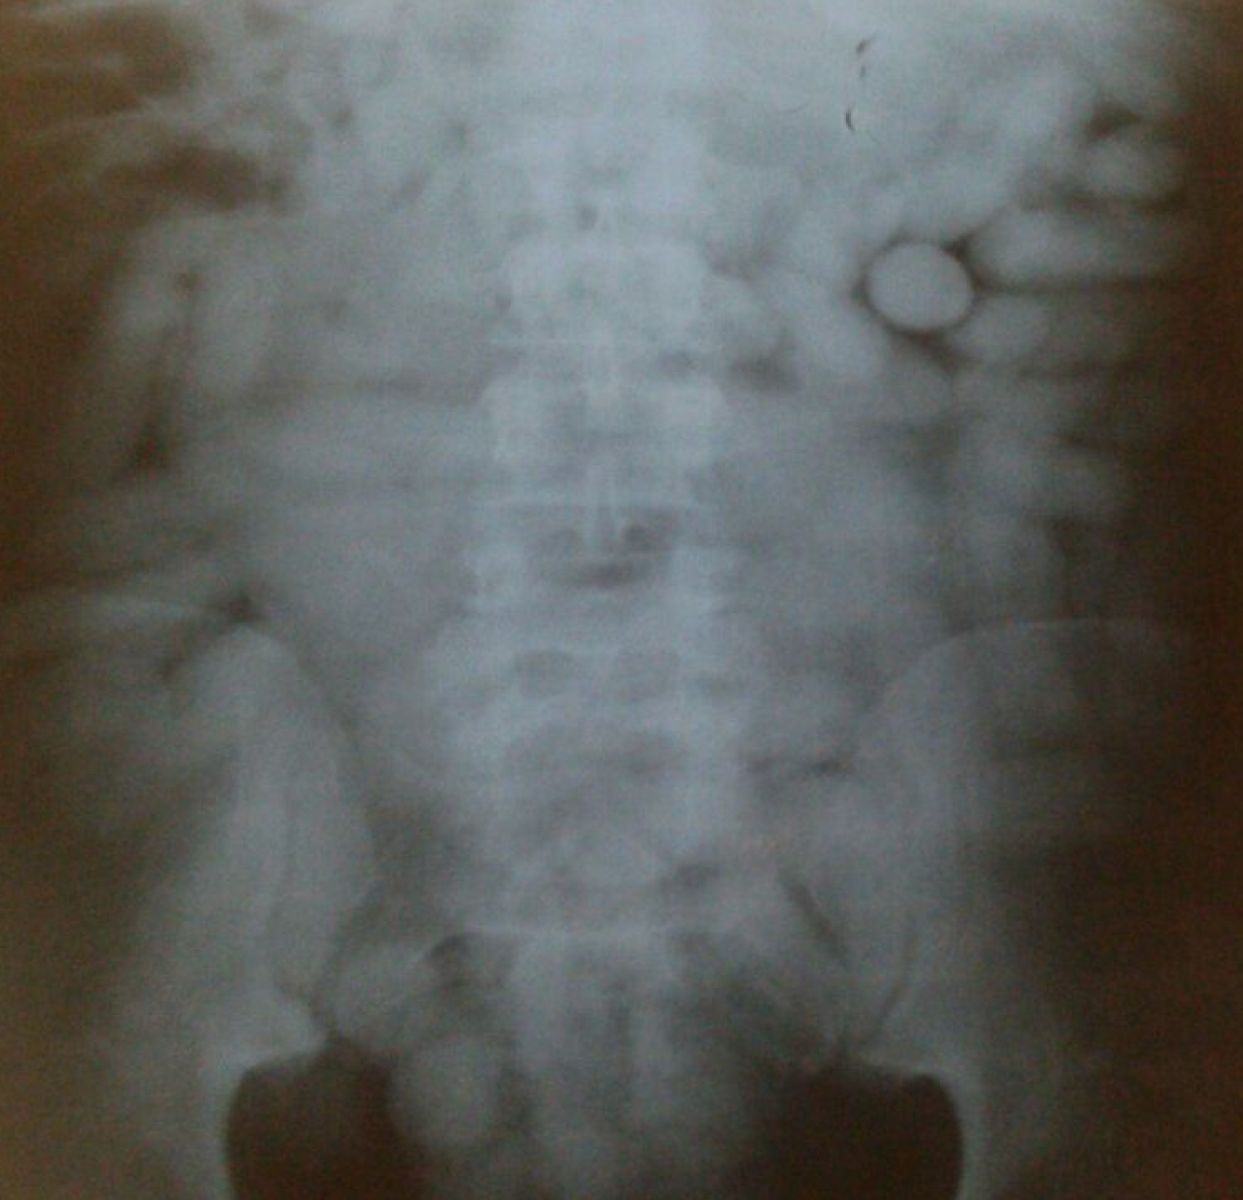

Raio x do suspeito feito na UPA da Imbiribeira.

Ao checar as bagagens dele, a polícia encontrou passagens aéreas para Cabo Verde, na África, que não constava na versão de José, que havia afirmado ter vindo fazer turismo no Recife. Em seguida, ele passou mal, se queixando de fortes dores no estômago. Foi então levado pelos policiais à UPA da Imbiribeira e diagnosticado, através de raio x, com 149 cápsulas de cocaína no estômago.